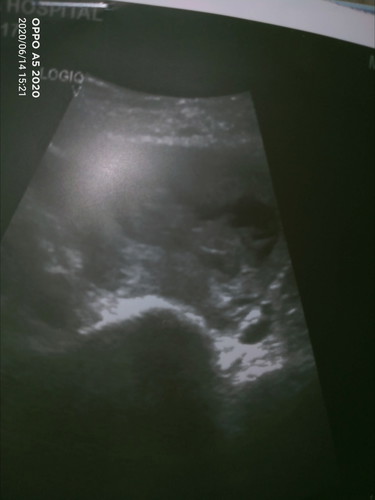

ท้องที่3อยู่ในภาวะแท้งคุกคาม

ตั้งครรภ์ได้11สัปดาห์ มีเลือดออกทางช่องคลอด หมอบอกอยู่ในภาวะแท้งคุกคาม เค้าจะอยู่กะเรามั้ยค่ะ ภาวนาขอให้เค้าอยู่